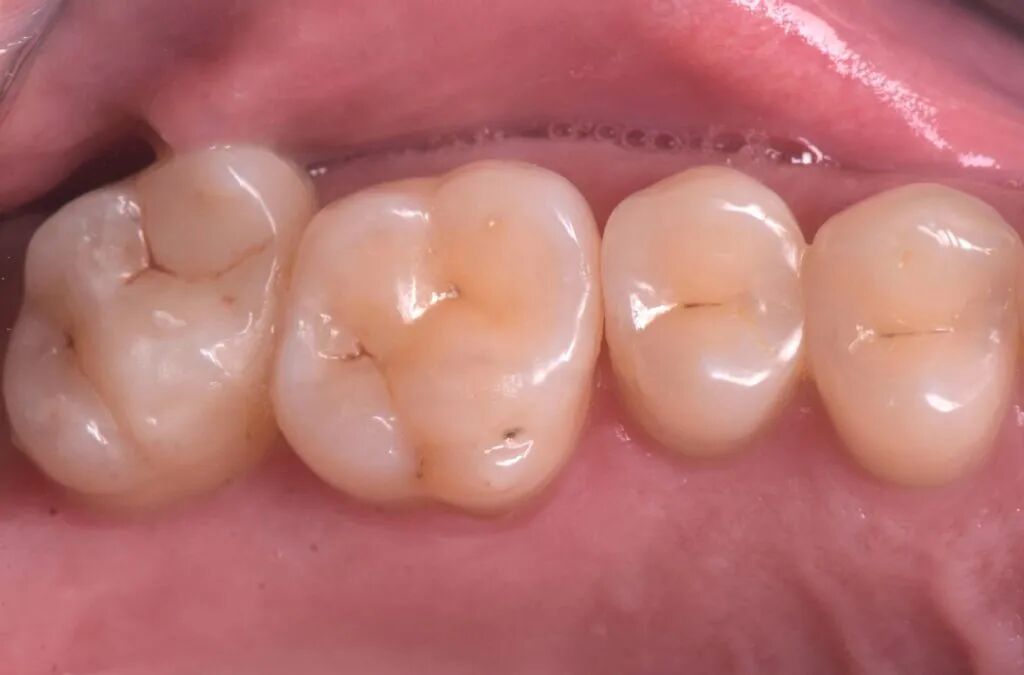

图17. 一个月回访。